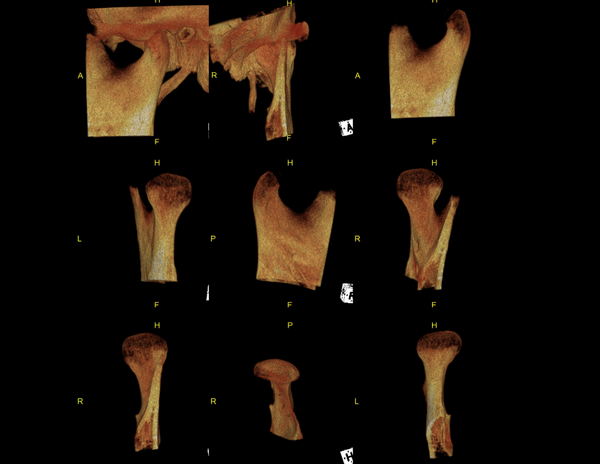

A Tomografia Computadorizada pela técnica do feixe cônico/cone beam (CBCT) introduziu um novo conceito de tomografia computadorizada na região bucomaxilofacial, que por meio da rápida aquisição volumétrica produz imagens com altíssimo grau de definição e fidelidade, além da redução na dose total de radiação emitida ao paciente.